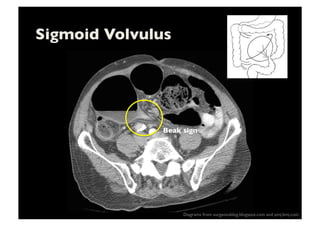

Sigmoid Volvulus

Twist around sigmoid mesocolon

Massive distension

Lack of haustration

Coffee bean shaped

classic- Rt dome

Diagrams from surgeonsblog.blogspot.com and pmj.bmj.com

Beak sign